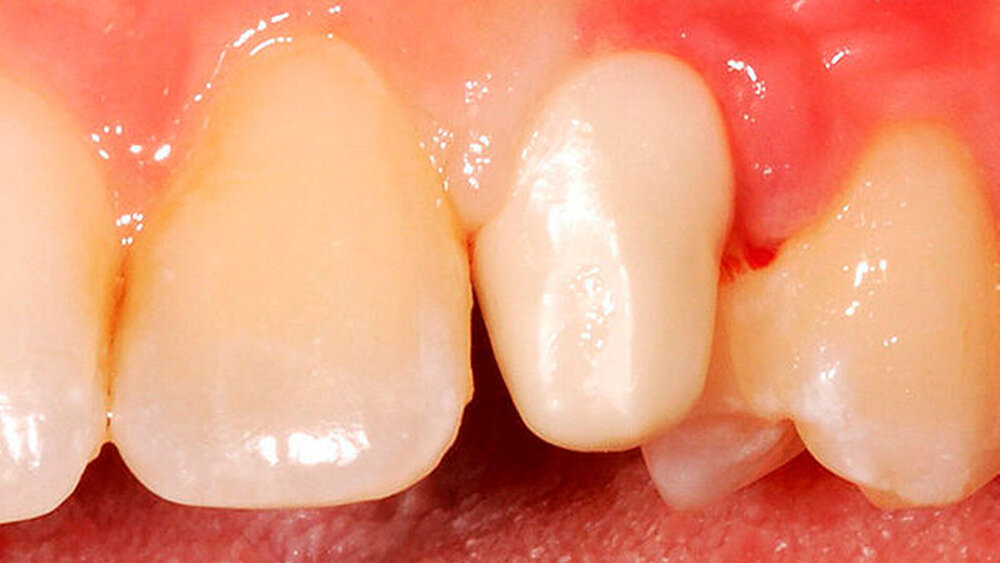

Auf jeden Fall! Neben einer besseren Ästhetik, gerade bei der Verwendung von Zirkon, ist die Lage des Übergangs Abutment-Krone bei zementierten Arbeiten von enormer Wichtigkeit. Werden aufgrund zu tief subgingival liegender Kronenränder Zementreste unzureichend entfernt, stellt dies eine der Hauptursachen für eine frühe Periimplantitis dar.

Definitiv. Bis kurz vor der Herstellung der Restauration kann ich entscheiden, ob ich das Abutment einteilig als Hybridkrone oder zweiteilig gestalte. Zudem ist ein Materialmix möglich: Aus Zirkonoxid plus Kunststoff lassen sich Langzeitprovisorien fertigen, das individuelle Kompositabutment kann man nach drei Monaten austauschen, um die Gingiva auszuformen. Oder man bleibt bei Lithiumdisilikat und setzt auf einteilige Hybridkronen.

Kunz:

Richtig, denn sitzt das Implantat zu hoch, können sich Schwierigkeiten bei der Ausbildung des Emergenzprofils ergeben. Angulationsprobleme lassen sich dagegen in der Regel mit Abutments ausgleichen.